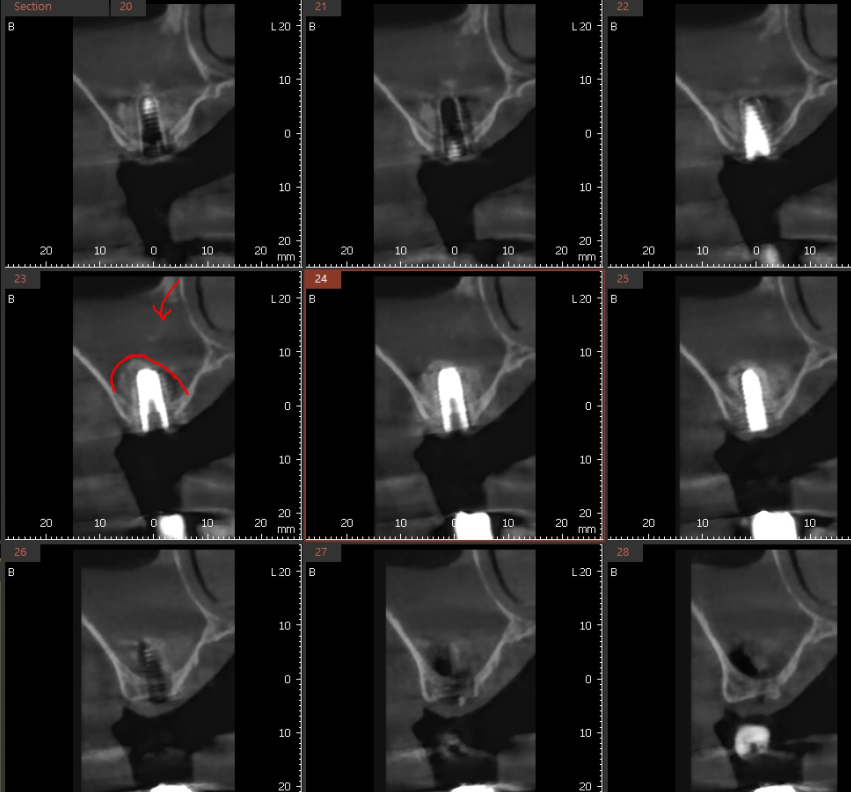

ct를 확인하면 미사 임플란트 시 이식된 뼈이식

확인이 가능하죠~

상악동 거상술을 통해 임플란트를 지탱할 충분한 뼈를 확보하면,

시술 후에도 임플란트가 튼튼하게 자리 잡을 수 있습니다!!